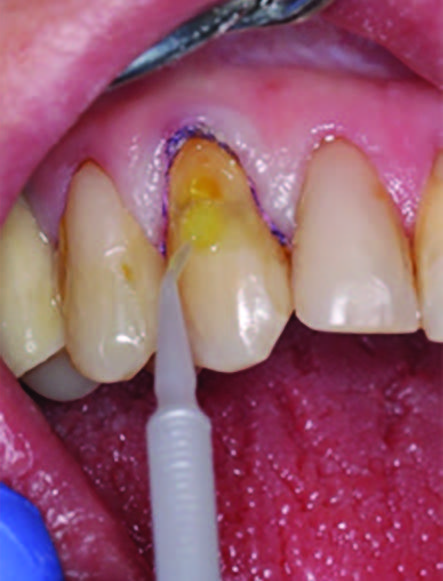

To improve isolation and soft tissue access, a retraction cord was placed before initiating the procedure (Fig. 2). The tooth was evaluated using a caries indicator dye (Kuraray Noritake Dental), helping to identify any remaining infected tissue beneath the dislodged composite (Fig. 3). Decay removal was completed with a diamond bur, and the enamel was bevelled using a starburst pattern to enhance aesthetic blending (Fig. 4). This preparation design was chosen for visual integration rather than bond strength enhancement.

Figure 4. Preparation of the lesion is completed with diamond bur and starburst beveling pattern to enhance aesthetic blending.